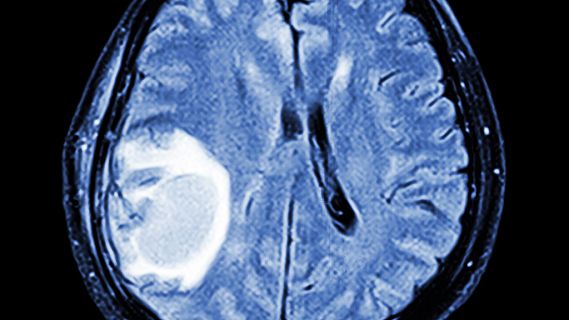

Nos interesamos por un nuevo sistema para operar tumores cerebrales considerados inoperables porque afectan a áreas funcionales. Nos los explica el doctor Juan Antonio Barcia, jefe del servicio de Neurocirugía del hospital Clínico San Carlos de Madrid, que lidera el equipo que ha probado con éxito este innovador (09/06/16).